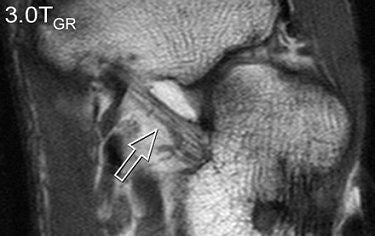

| A 31-year-old healthy male volunteer. Axial T1-weighted fast spin-echo images of foot show superior delineation of spring ligament (arrow) at 3 T (top and middle) as opposed to 1.5 T (below); 3.0TGR = 3.0T with GRAPPA algorithm. No significant difference was found between (top) and parallel (middle) acquisitions at 3 T; visualization of this ligament was rated very good at 3 T and as moderate at 1.5 T (below) by both radiologists. |

According to the results, GRAPPA MR resulted in a 44% reduction in scan time compared with conventional imaging. SNRs and CNRs doubled on the SPGR sequence at 3 tesla. These 3-tesla images also demonstrated comparable edge sharpness.

Image quality was rated highest on 3-tesla images. The axial T1-weighted sequence was given an average score of 3.4 at 3 tesla for parallel and normal acquisitions versus a score of 2.8 for 1.5 tesla. Visualization of ligaments and tendon abnormalities were also rated highly on parallel 3-tesla MR.